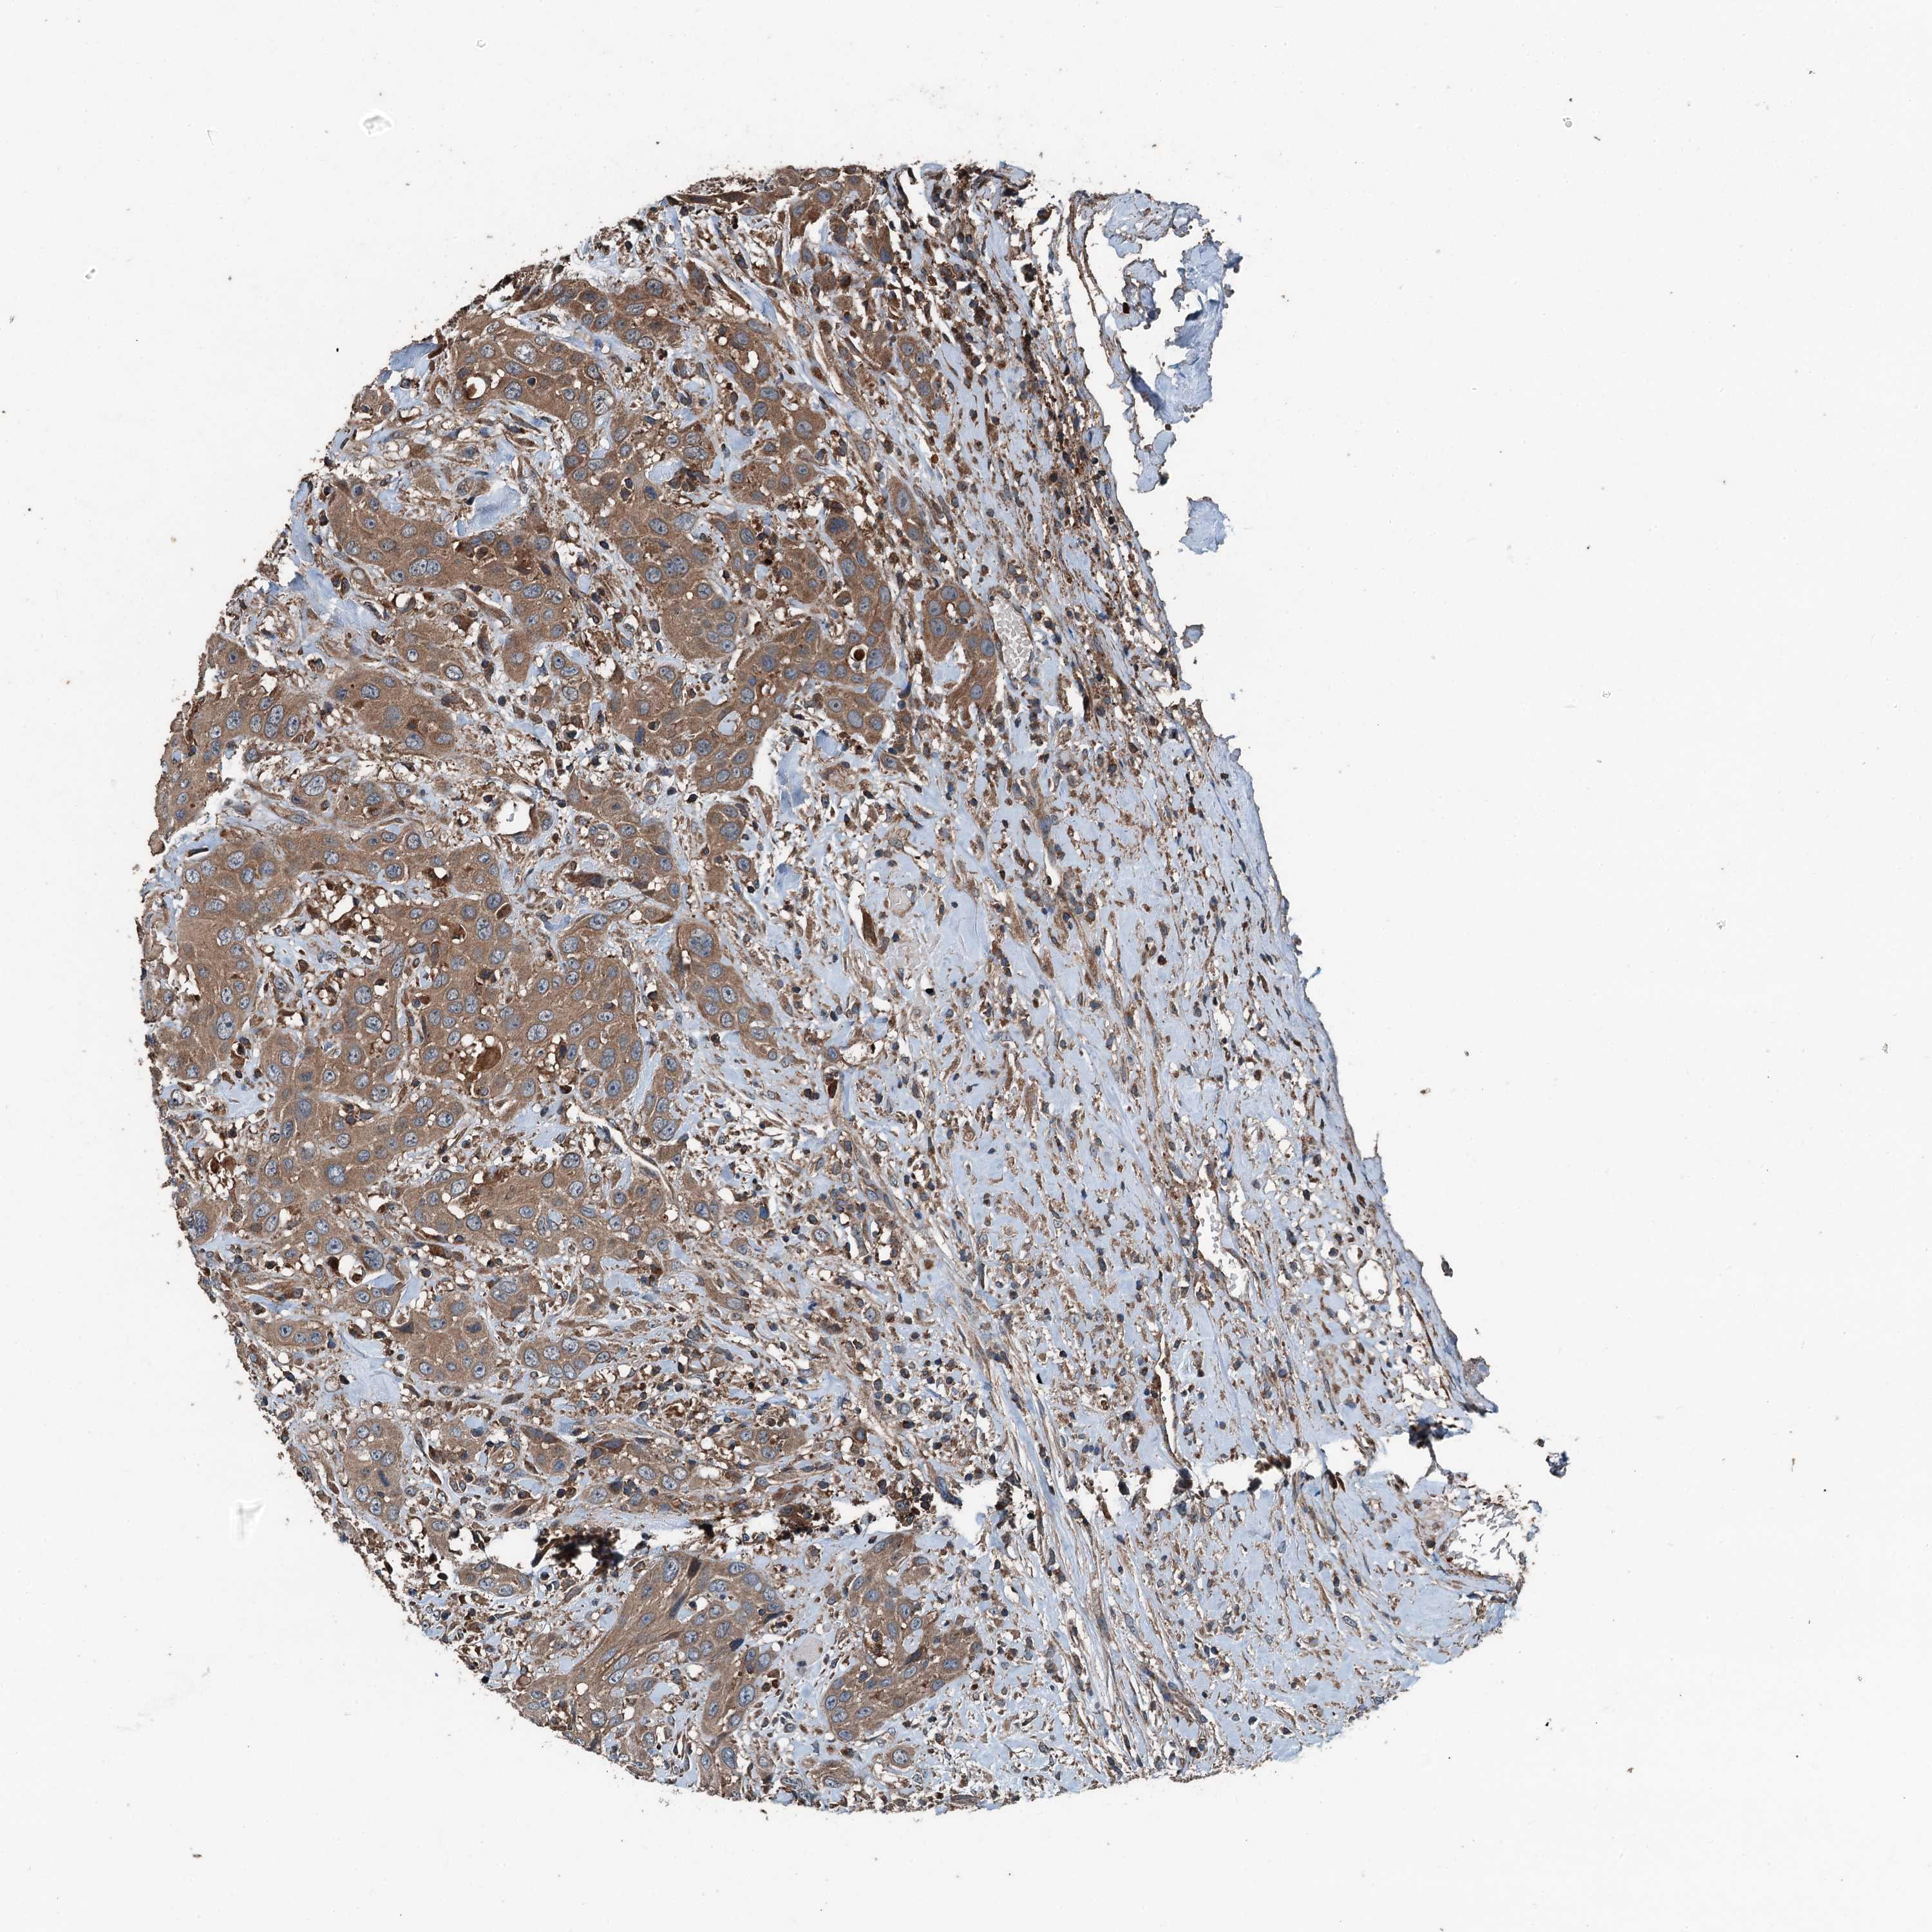

HEAD AND NECK CANCER - Protein expressioni

A mouse-over function shows sample information and annotation data. Click on an image to view it in a full screen mode. Samples can be filtered based on level of antibody staining by selecting one or several of the following categories: high, medium, low and not detected. The assay and annotation is described here.

Antibody stainingi

Antibody staining in the annotated cell types in the current human tissue is reported as not detected, low, medium, or high, based on conventional immunohistochemistry profiling in selected tissues. This score is based on the combination of the staining intensity and fraction of stained cells.

Each image is clickable and will lead to virtual microscopy that enables deeper exploration of all samples and also displays staining intensity scores, fraction scores and subcellular localization as well as patient and tissue information for each sample.

Antibody HPA041227

Squamous cell carcinoma, NOS

Squamous cell carcinoma, metastatic, NOS

Adenocarcinoma, NOS